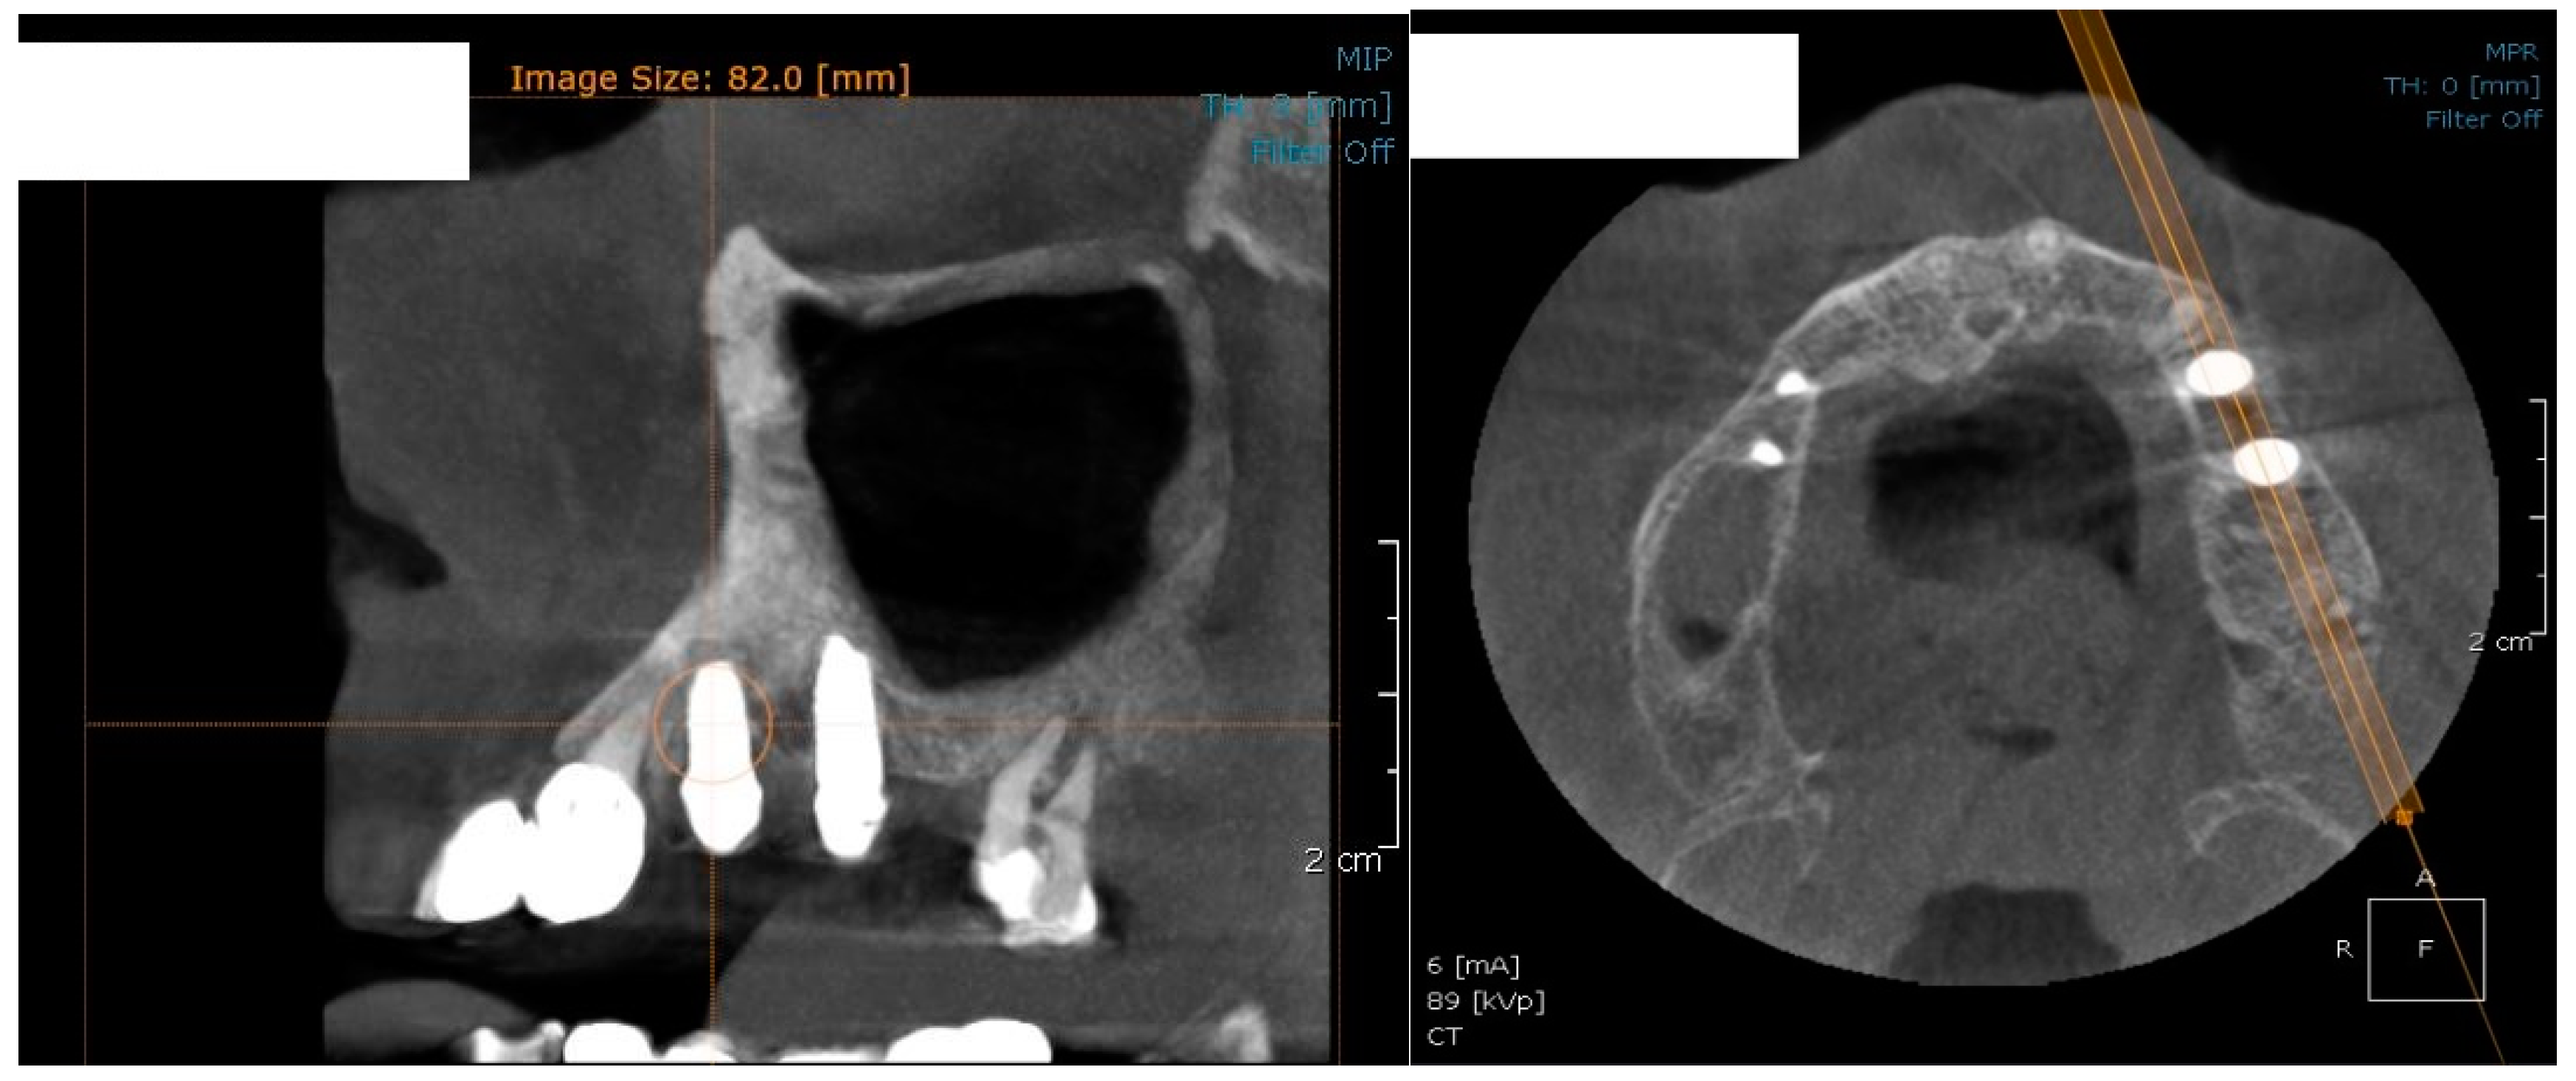

For image acquisition, we used a ProMax 3D CBCT unit (Planmeca, Helsinki, Finland), with the previously mentioned settings. Images were acquired and saved in JPEG format. To locate implant target sites, bone density, and to record the mean CT number of the trabecular bone from these sites, we used the OnDemand 3Ddata App™ software (Cybermed Inc., Seoul, South Korea). In each site, our region of interest was a square volume of bone located within the alveolar ridge (Figure 3, Figure 4 and Figure 5). All data recorded were input into the Microsoft Office Excel™, 2017 version, analysis software (Microsoft, Redmond, WA, USA).

Figure 3.

CBCT images used in the study, showing sagittal sections of bone.

Figure 4.

CBCT images used in the study showing the density of bone.